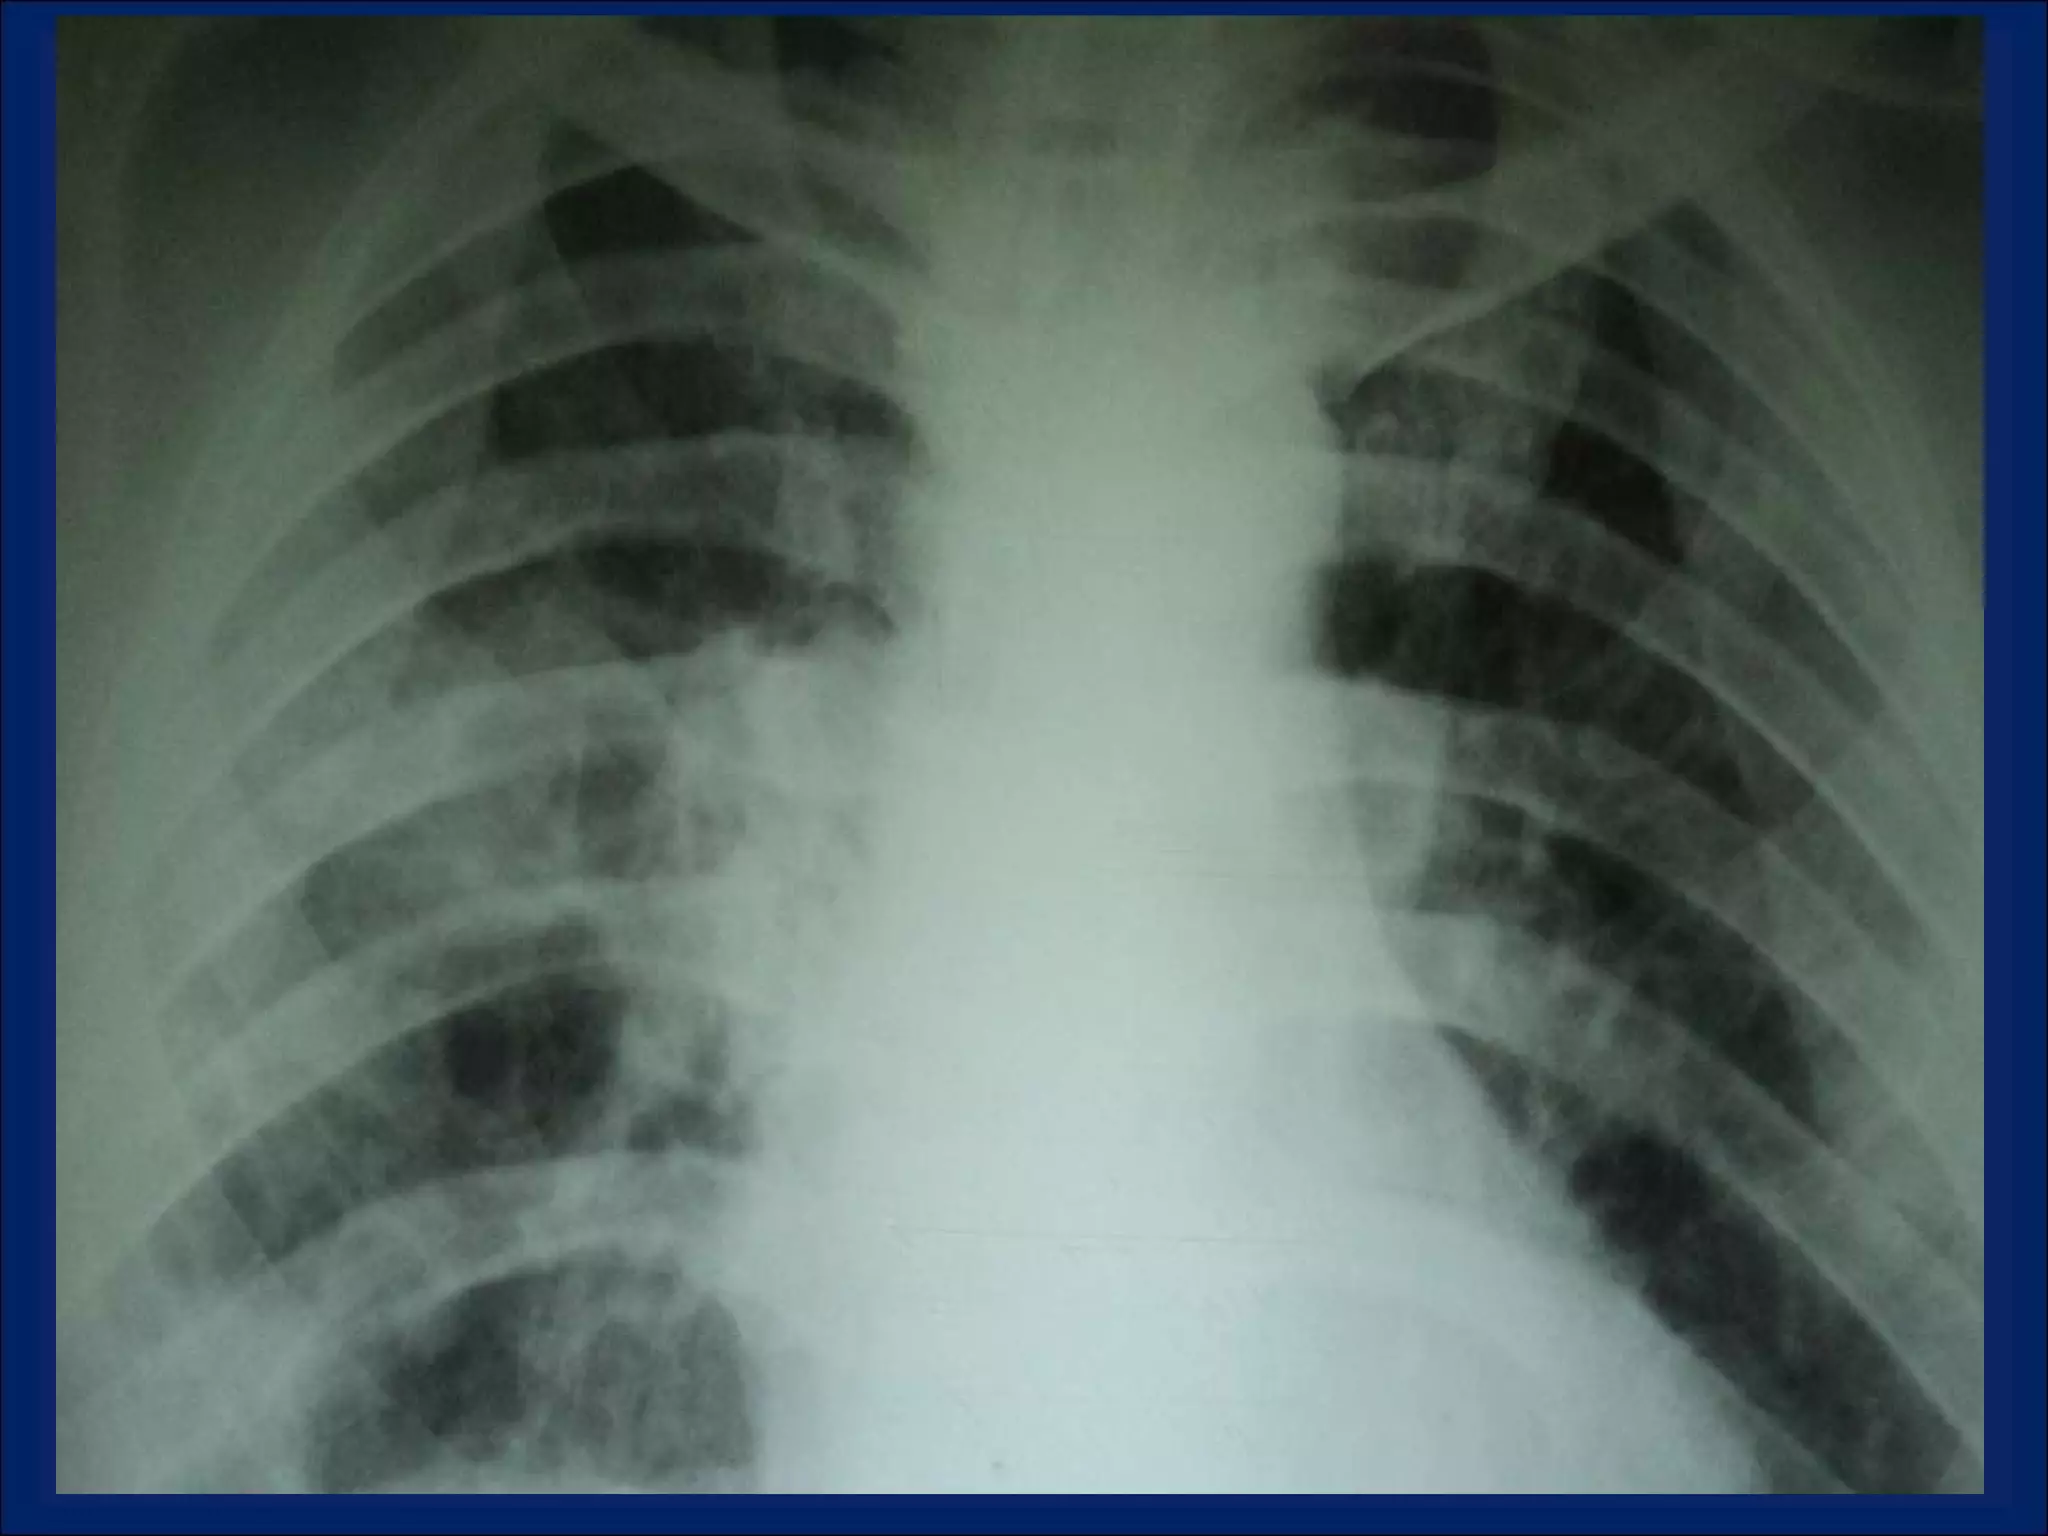

Imaging: Multiple Pulmonary Cavitary Lesions

LOOKING  AT  CAVITIES What is the anatomic distribution?  Is It single or multiple?  If multiple , are they focally located or diffusely seen in multiple lobes of both lungs? Is are the characteristics of the cavity? Is the cavity wall thick or thin? Is the interior lining nodular, shaggy, or smooth? Are there any other associated radiographic abnormalities?